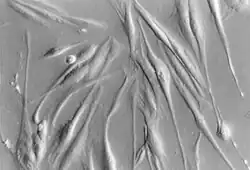

Im Ruhezustand sind Pankreassternzellen in der Lage, Fett und Vitamin A zu speichern. Im aktivierten Zustand erlangen sie myofibroblastäre Eigenschaften, indem sie Aktin-Fasern herstellen, die im Inneren der Zelle vorliegen und eine Migration der Zelle ermöglichen, und indem sie Bestandteile der bindegewebigen Extrazellularmatrix, insbesondere Kollagen-Fasern, herstellen, die dann aus der Zelle heraus in das Interstitium sezerniert werden.[1][2]